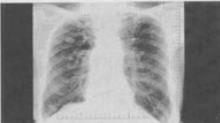

- 单项选择题3、 患者男,69岁,胸闷气逼多年,近来咳嗽,无胸痛、无痰中带血,X线检查如图,最可能的诊断是()。

A、慢支肺气肿、右上肺肿瘤

B、慢支肺气肿、右上肺炎性假瘤

C、慢支肺气肿、右上肺结核瘤

D、慢支肺气肿、肺转移瘤

E、慢支肺气肿、结节病